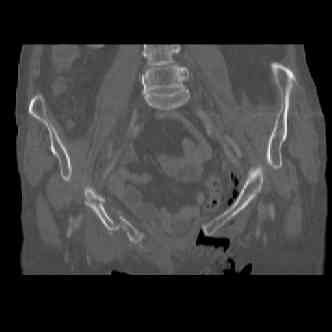

attached are several CT cuts. please let me know if you need more. the CT is pre-pelvic ex-fix placement.

injuries are limited to the pelvis. left rami open and visible in a 10cm vertical laceration just lateral to left labia majora. wound is grossly clean. no vaginal and no urinary issues. CT scan shows widening of both SI joints anteriorly but I think this is vertically stable pattern.

pt treated that night with I/D and supra-acetabular frame to close the ring. consideration was given for SI screws bilateraly, but given time of night and other factors decision made not to proceed.